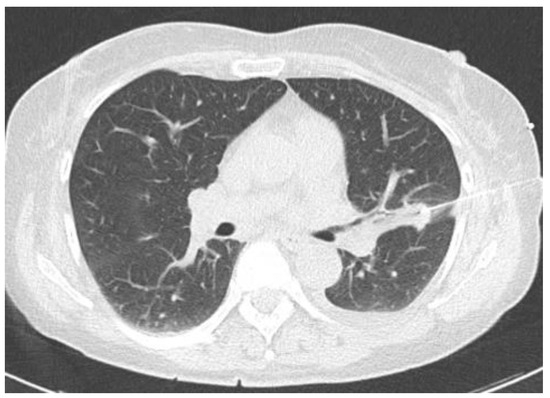

2.2.1. TIME 0: Lesion marking and SPECT Analysis